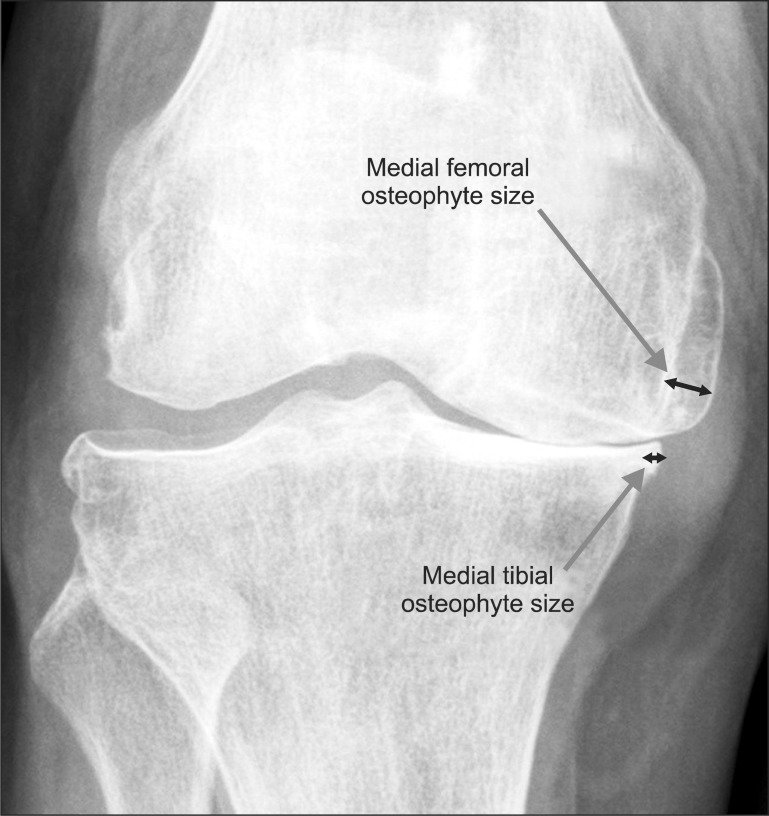

All a joint is two bones coming together with a bunch of stuff in between those bones called cartilage and then ligaments holding it together and the cartilage is meant to be a buffer in between the two bones. Your body doesn't want bone-on-bone it will fight against bone on bone. In fact, the body will create these things called osteophytes. They're little bones that stick out almost like teeth. That's trying to create separation so that the bones don't touch because it doesn't want friction.

Typically, they've nicknamed osteophytes with the term bone spurs. They can happen on your spine, they can happen on the heel of your foot if your gait is off and your body is trying to create space between the floor. So if your cartilage is decaying and the bones are touching, your body is going to create these bone spurs to create space and that may cause some cracking.